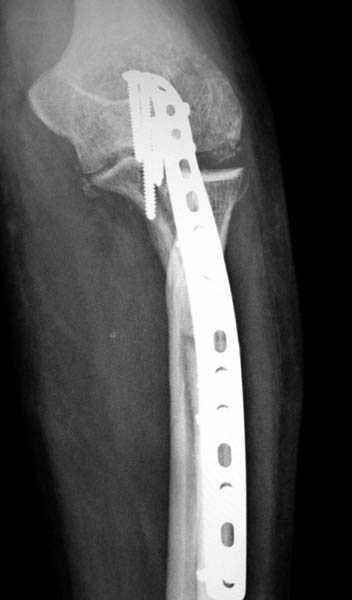

Здесь выставлены несколько случаев и варианты фиксации локтевого отростка, некоторые в комбинации с другими переломами.

1 вариант применен ACUMED локинг пластина

2 вариант

перелом локтевого отростка с переломом головки лучевой кости (использованы 2 мм шурупы)

3 вариант

перелом с capitelum humerus и проксимальной трети улна